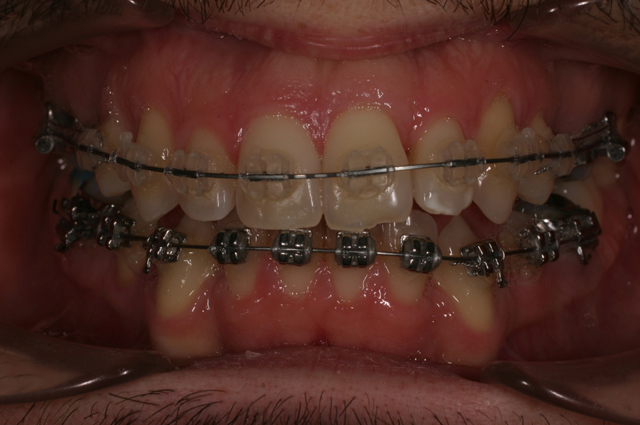

Il soggetto di sesso maschile si è presentato alla nostra osservazione per la correzione dell'affollamento dentario.

Secondo noi il caso il caso non poteva essere trattato senza estrazioni. Come si può notare a fine terapia, l'estrazione dei secondi premolari ha permesso un buon controllo dell'ancoraggio anteriore e quindi il mantenimento del profilo dentario. Inoltre,la corretta gestione degli ancoraggi ha permesso di non avere alcuna comparsa di corridoi scuri laterali. La corretta gestione degli ancoraggi conferma il fatto che anche un caso estrattivo ha una ottima riuscita estetica.

Trattamento: Estrazione di 1.5 e 2.5 superiormente con ancoraggio con un bottone di Nance

Estrazioni inferiori di 3.4 e 4.4 con arco linguale

Tecnica MBT con chiusura degli spazi per arretramento in massa.

Finitura e contenzione con essix superiore e retainer inferiore.